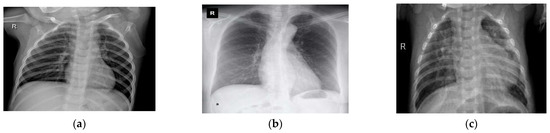

Chest X-ray images were also used to extend and enhance this experimentation. A total of 5935 X-ray images containing 4273 X-rays for pneumonia, 1583 X-rays for healthy chests, and 79 X-rays for COVID-19-affected chests were collected from two separate open-access sources [33,34]. Curated X-ray images from both datasets are shown in Figure 2. After this, 85% of the datasets were used for training and 15% for testing. In DL applications, i.e., in the COVID-19 diagnosis literature, these datasets have been publicly used, and their efficiency and effectiveness have also been proven. In the case of training, if these merged datasets can be used, then the generalization of various DL models is expected to improve. The details of the dataset are listed in Table 2 and Table 3. After that, a balanced X-ray dataset is taken into consideration [51]. This balanced dataset is actually a collection of four different open-source datasets of X-ray images [53,54,55,56]. This dataset has undergone some preliminary processing, such as the merging of the datasets and the resizing of the images. In the end, we shuffled the data and converted all of the images from grayscale to RGB format.

Figure 2.

A sample of the experimental chest X-ray dataset: (a) normal or healthy chest, (b) COVID-19, and (c) pneumonia.